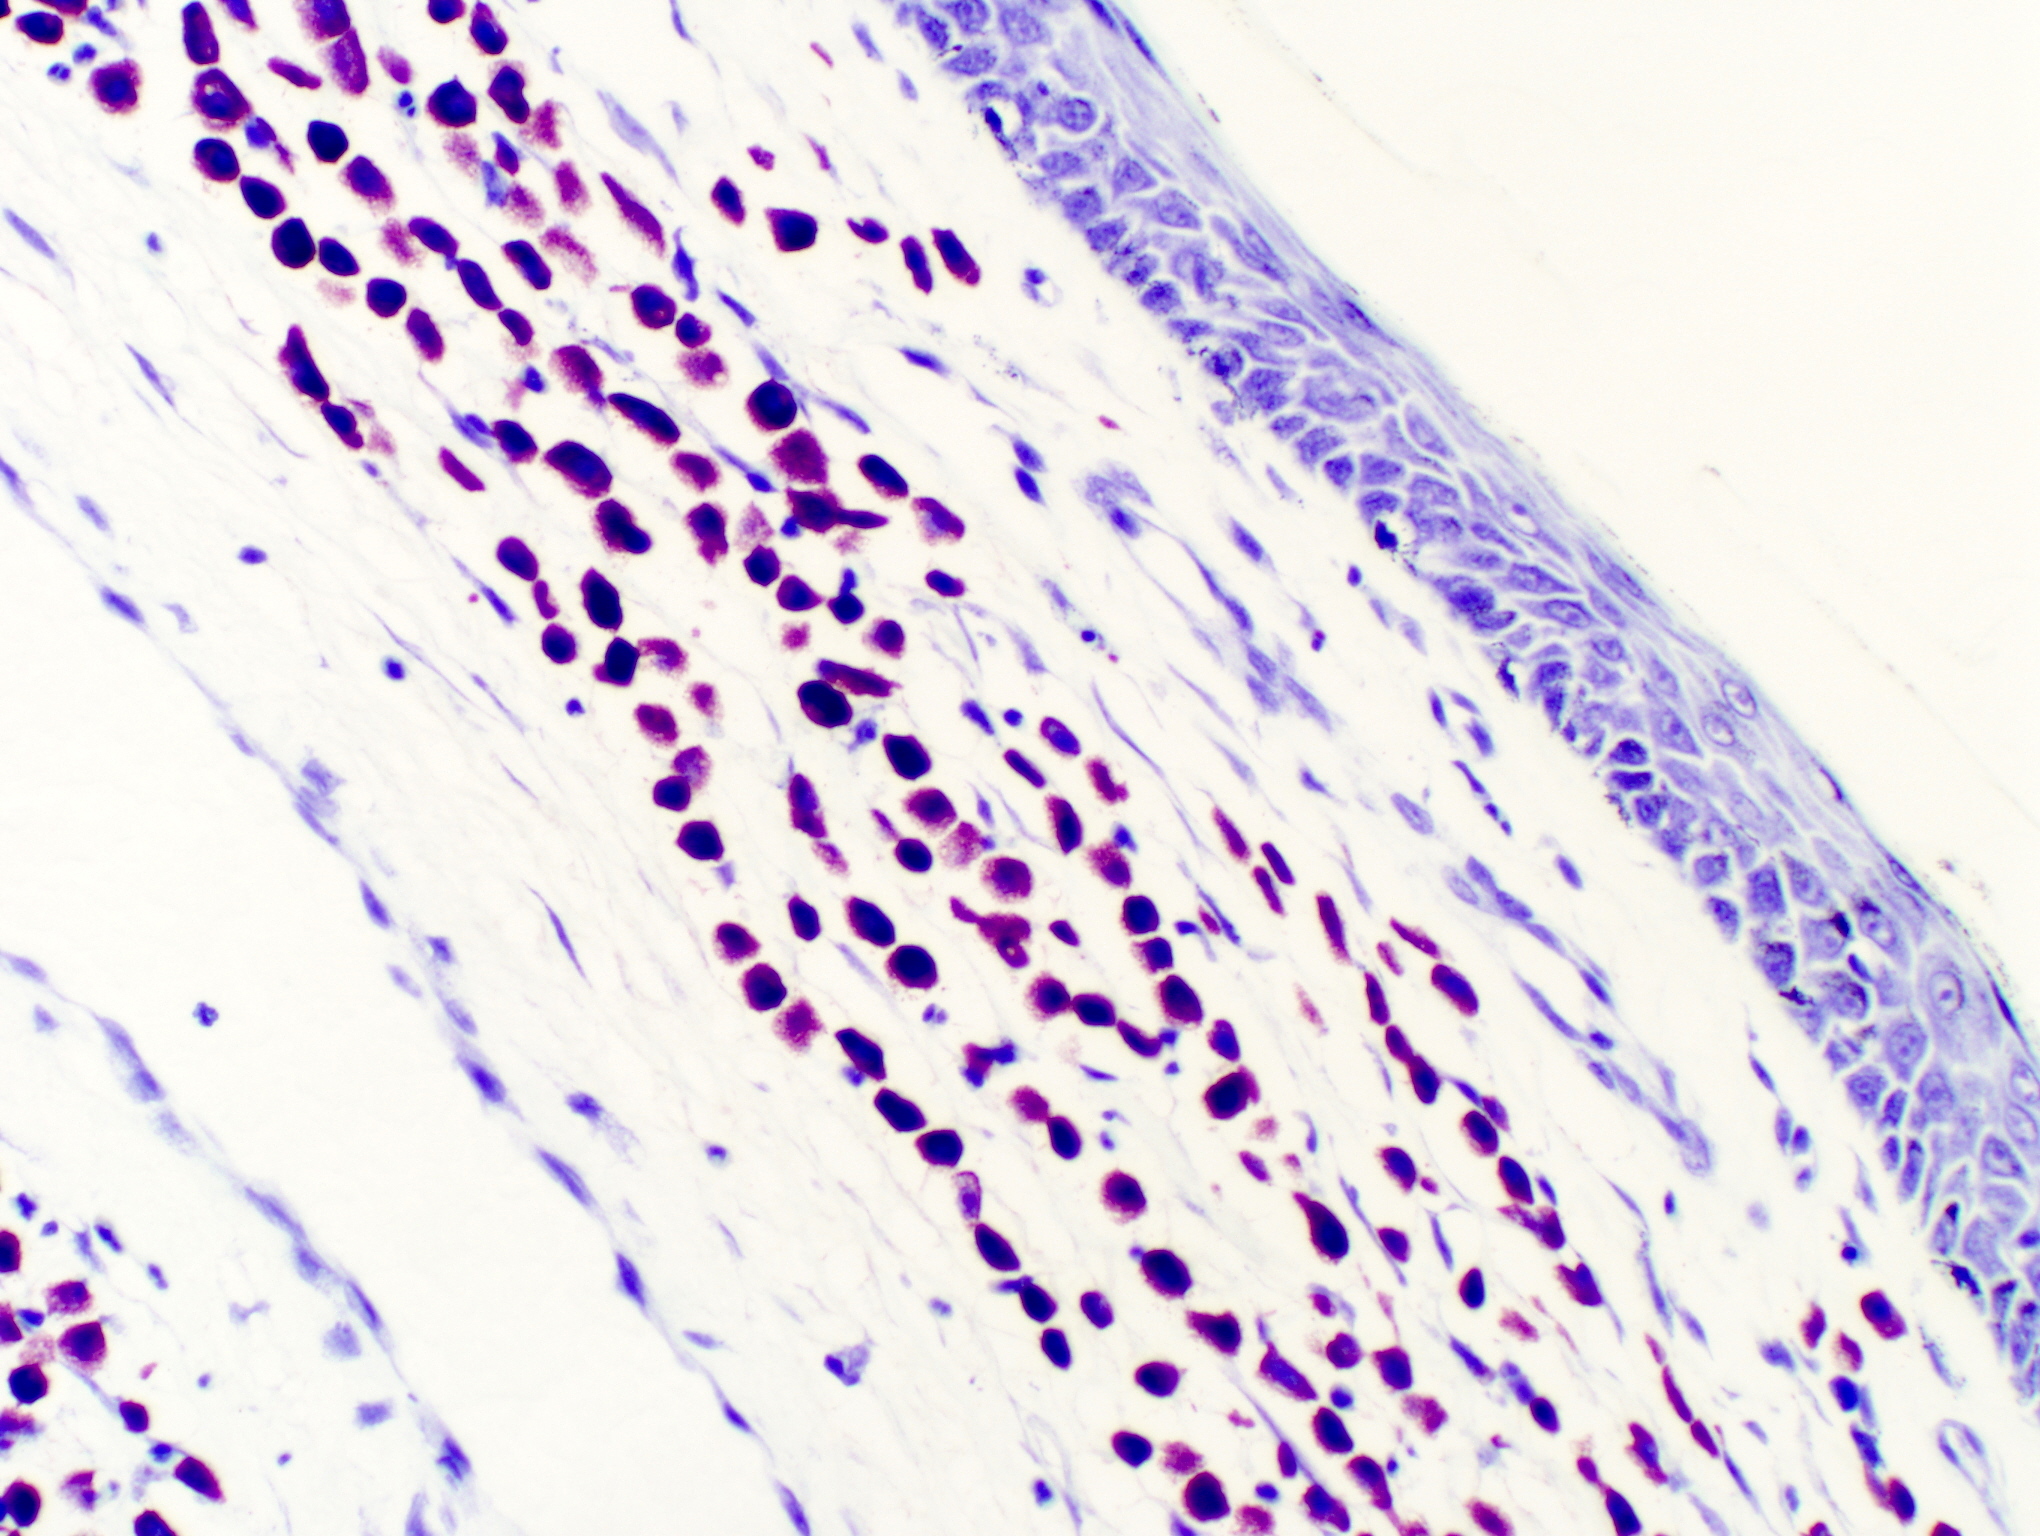

Q: How is Mast Cell Tumor diagnosed? A: Diagnosis typically combines physical examination, fine-needle aspiration, and biopsy. These tests confirm mast cell presence, assess malignancy levels, and guide treatment planning.

🔑 Mast Cell Tumor Boston Terrier 📂 General 🏷️ Signs ofMast Cell Tumor Dogs 🏷️ Mast Cell TumorOn Dog 🏷️ Dog Mast Cell TumorOn Leg 🏷️ Mast Cell Tumorin Dog Mouth 🏷️ Mast Cell TumorOn Dog Head 🏷️ Dog Mast Cell TumorSymptoms 🏷️ Canine Mast Cell TumorCytology 🏷️ Boxer DogMast Cell Tumor 🏷️ Mast Cell TumorTreatment in Dogs 🏷️ FelineMast Cell Tumor 🏷️ Mast Cell TumorOn Dog Paw 🏷️ Cutaneous Mast Cell TumorDog 🏷️ Mast Cell TumorCat 🏷️ CanineMast Cells 🏷️ Mast Cell Tumorin Boxers 🏷️ Mast CellTumours Dogs 🏷️ Mast Cell TumorDog Ear 🏷️ Mast Cell TumorRemoval Dog 🏷️ Mast Tumor Cellfor Dogs 🏷️ Mast Cell TumorGolden Retriever 🏷️ MalignantMast Cell Tumor 🏷️ MCT Dog 🏷️ Mast Cell TumorRupture 🏷️ Mast CellTumour Pug 🏷️ Small Mast Cell TumorDog 🏷️ Digit Mast CellTumour Dog 🏷️ Mast Cell TumorPitbull 🏷️ Mast Cell TumorDog Appearance 🏷️ FerretMast Cell Tumor 🏷️ Benadryl for Dogs withMast Cell Tumors 🏷️ Mast Cell TumorDog Nose 🏷️ Mast Cell TumorOn Dog Skin Cancer 🏷️ Mast Cell TumorVeterinary Partner 🏷️ Mast CellDog Lip 🏷️ Dog Mast Cell TumorSupplement 🏷️ Mast Cell TumorBulldog 🏷️ Mast CellDog Toe 🏷️ Dog Eye Cancer 🏷️ Ruptured Mast Cell TumorCanine 🏷️ Dog Mast Cell TumorOn Muzzle 🏷️ Mast Cell TumorUnder Microscope 🏷️ Mast Cell TumorOn Ultrasound of a Dog 🏷️ Grade 1Mast Cell Tumor Dog 🏷️ Boston TerrierSkin Cancer 🏷️ Mast Cell TumorsRhodesian Ridgeback 🏷️ Boston TerrierTemperament 🏷️ Mast Cell TumorTreatmentn in Dogs 🏷️ Mastocytoma Dog 🏷️ Spindle Cell Tumorin Boston Terrier 🏷️ BullTerrier Mast Cell Tumor